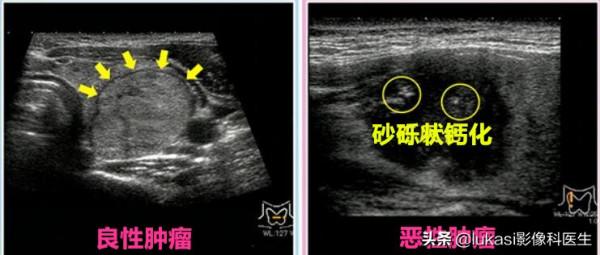

左側為良性腫瘤。界線分明,與正常地方的區別一目瞭然。

右側的惡性腫瘤邊界模糊。中間能看到的白色東西就是砂礫狀的鈣化部分。現在檢測裝置的精度很高,可以可靠地檢測 1 釐米或更小的腫瘤。